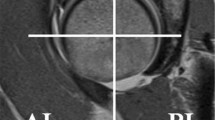

In our qualitative analysis, the shape and signal intensity of the LTL proximal zone, and the direction of high-signal-intensity direction inside the proximal zone were evaluated by consensus of two muskuloskeletal radiologists (HY, TU) using a 2D GRE sequence. The shape of the LTL proximal zone was classified into five types (type 1: regular triangle, type 2: broad-based triangle, type 3: narrow-based triangle, type 4: asymmetrical triangle, and type5: bar shape; Fig. 1). Our study chose the slice in which the largest triangle was found, and signal characteristics in the proximal LTL were evaluated in the same slice. The signal intensity of the LTL proximal zone was classified into three types (type 1: homogeneously low intensity, type 2: linear intermediate or high signal intensity traversing the distal surface, and type 3: linear intermediate or high intensity traversing both proximal and distal surfaces; Fig. 2) [6]. Among type 2 and type 3 signal intensities, the direction of intermediate or high signal intensity inside the proximal zone was classified into five types (type 1: radius–radius (RR) pattern, type 2: radius–ulna (RU) pattern, type 3: ulna–radius (UR) pattern, type 4: ulna–ulna (UU) pattern, and type 5: center (c) pattern) (Figs. 3 and 4). The RR pattern indicated high signal intensity traversing the radial side of the distal surface toward the radial side of the proximal surface, and the RU pattern indicated high signal intensity traversing the radial side of the distal surface toward the ulnar side of the proximal surface. The center pattern shows high signal intensity traversing the center of the proximal zone. The Mann-Whitney U-test was used to determine the significance of the differences in ages among analyzed groups. In each analysis, a P value of ≤0.05 was considered significant.

With thin sections in our study, the triangular shape of the LTL proximal zone could be consistently discerned over several slices. In addition, the linear shape was seen more often in or near the volar zone than in the proximal zone. Therefore, each subject had both linear and triangle shapes. The LTL in 77 of 90 subjects (85.6%) was found to be triangular-shaped (types 1-4) low signal intensity. The regular triangular shape (type 1) was most frequent (41.1%), followed by the broad-based triangle (type 2, 20.0%) and the asymmetrical triangle (type 3, 17.8%) (Table 1). The bar-shaped ligament was seen in only one patient. The LTL of 12 patients was not classified; one showed lunotriquetral coalition, one was not classified due to motion artifact, and ten were not classified due to difficulty of tracing a definite shape. These ten patients ranged in age from 34 to 67 years; their mean age was 53.4 years, making them significantly older than the remaining patients (p<0.0001) or normal volunteers (p<0.0001). All volunteers were found to have triangular-shaped LTL. Out of 77 patients with a triangular-shaped LTL proximal zone, the percentage of each signal intensity type was as follows; 33.8% type 1, 45.5% type 2, and 20.8% type 3 (Table 2). Two-thirds showed intermediate or high intensity inside the proximal LTL. Eight (30.8%) out of 26 patients with type 2 signal intensity showed linear high signal intensity on STIR images, while no type 3 patients did (Fig. 5). Of patients with non-classified LTL shape, six showed high signal intensity in the proximal zone with STIR. These cases could have suffered LTL tears. However, arthroscopy examination was not performed in five cases, because they were judged to have no indication for arthroscopy after MRI and physical examination. In one case, the proximal LTL could not be observed due to severe ulnotriquetral ligament injury on arthroscopy. Intermediate or high-signal-intensity direction pattern inside the proximal zone was assessed in the type 2 and type 3 signal-intensity patterns. RR and RU patterns were most frequent (both patterns were found in 29.4% of 51 subjects; Table 3). Both volunteers and patients with suspicion of TFCC injury revealed similar distribution in signal-intensity and high-signal-intensity direction characteristics (Tables 2 and 3).

a GRE image shows type 2 LTL signal intensity (linear intermediate or high signal intensity traversing the distal surface) (arrow). There is a small amount of fluid collection adjacent to distal surface of the proximal zone with (b) STIR sequence (arrow), while no signal intensity or morphological change is seen in proximal area inside the LTL with STIR, suggesting no injury